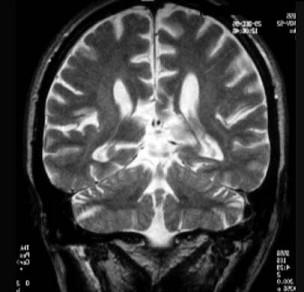

问题 根据MRI示最可能的诊断是 ( )

选项 A、脑室内出血 B、基底节钙化 C、脑白质软化 D、皮质萎缩或萎缩性脑叶硬化 E、胼胝体发育不良 一、单项选择题

答案 E